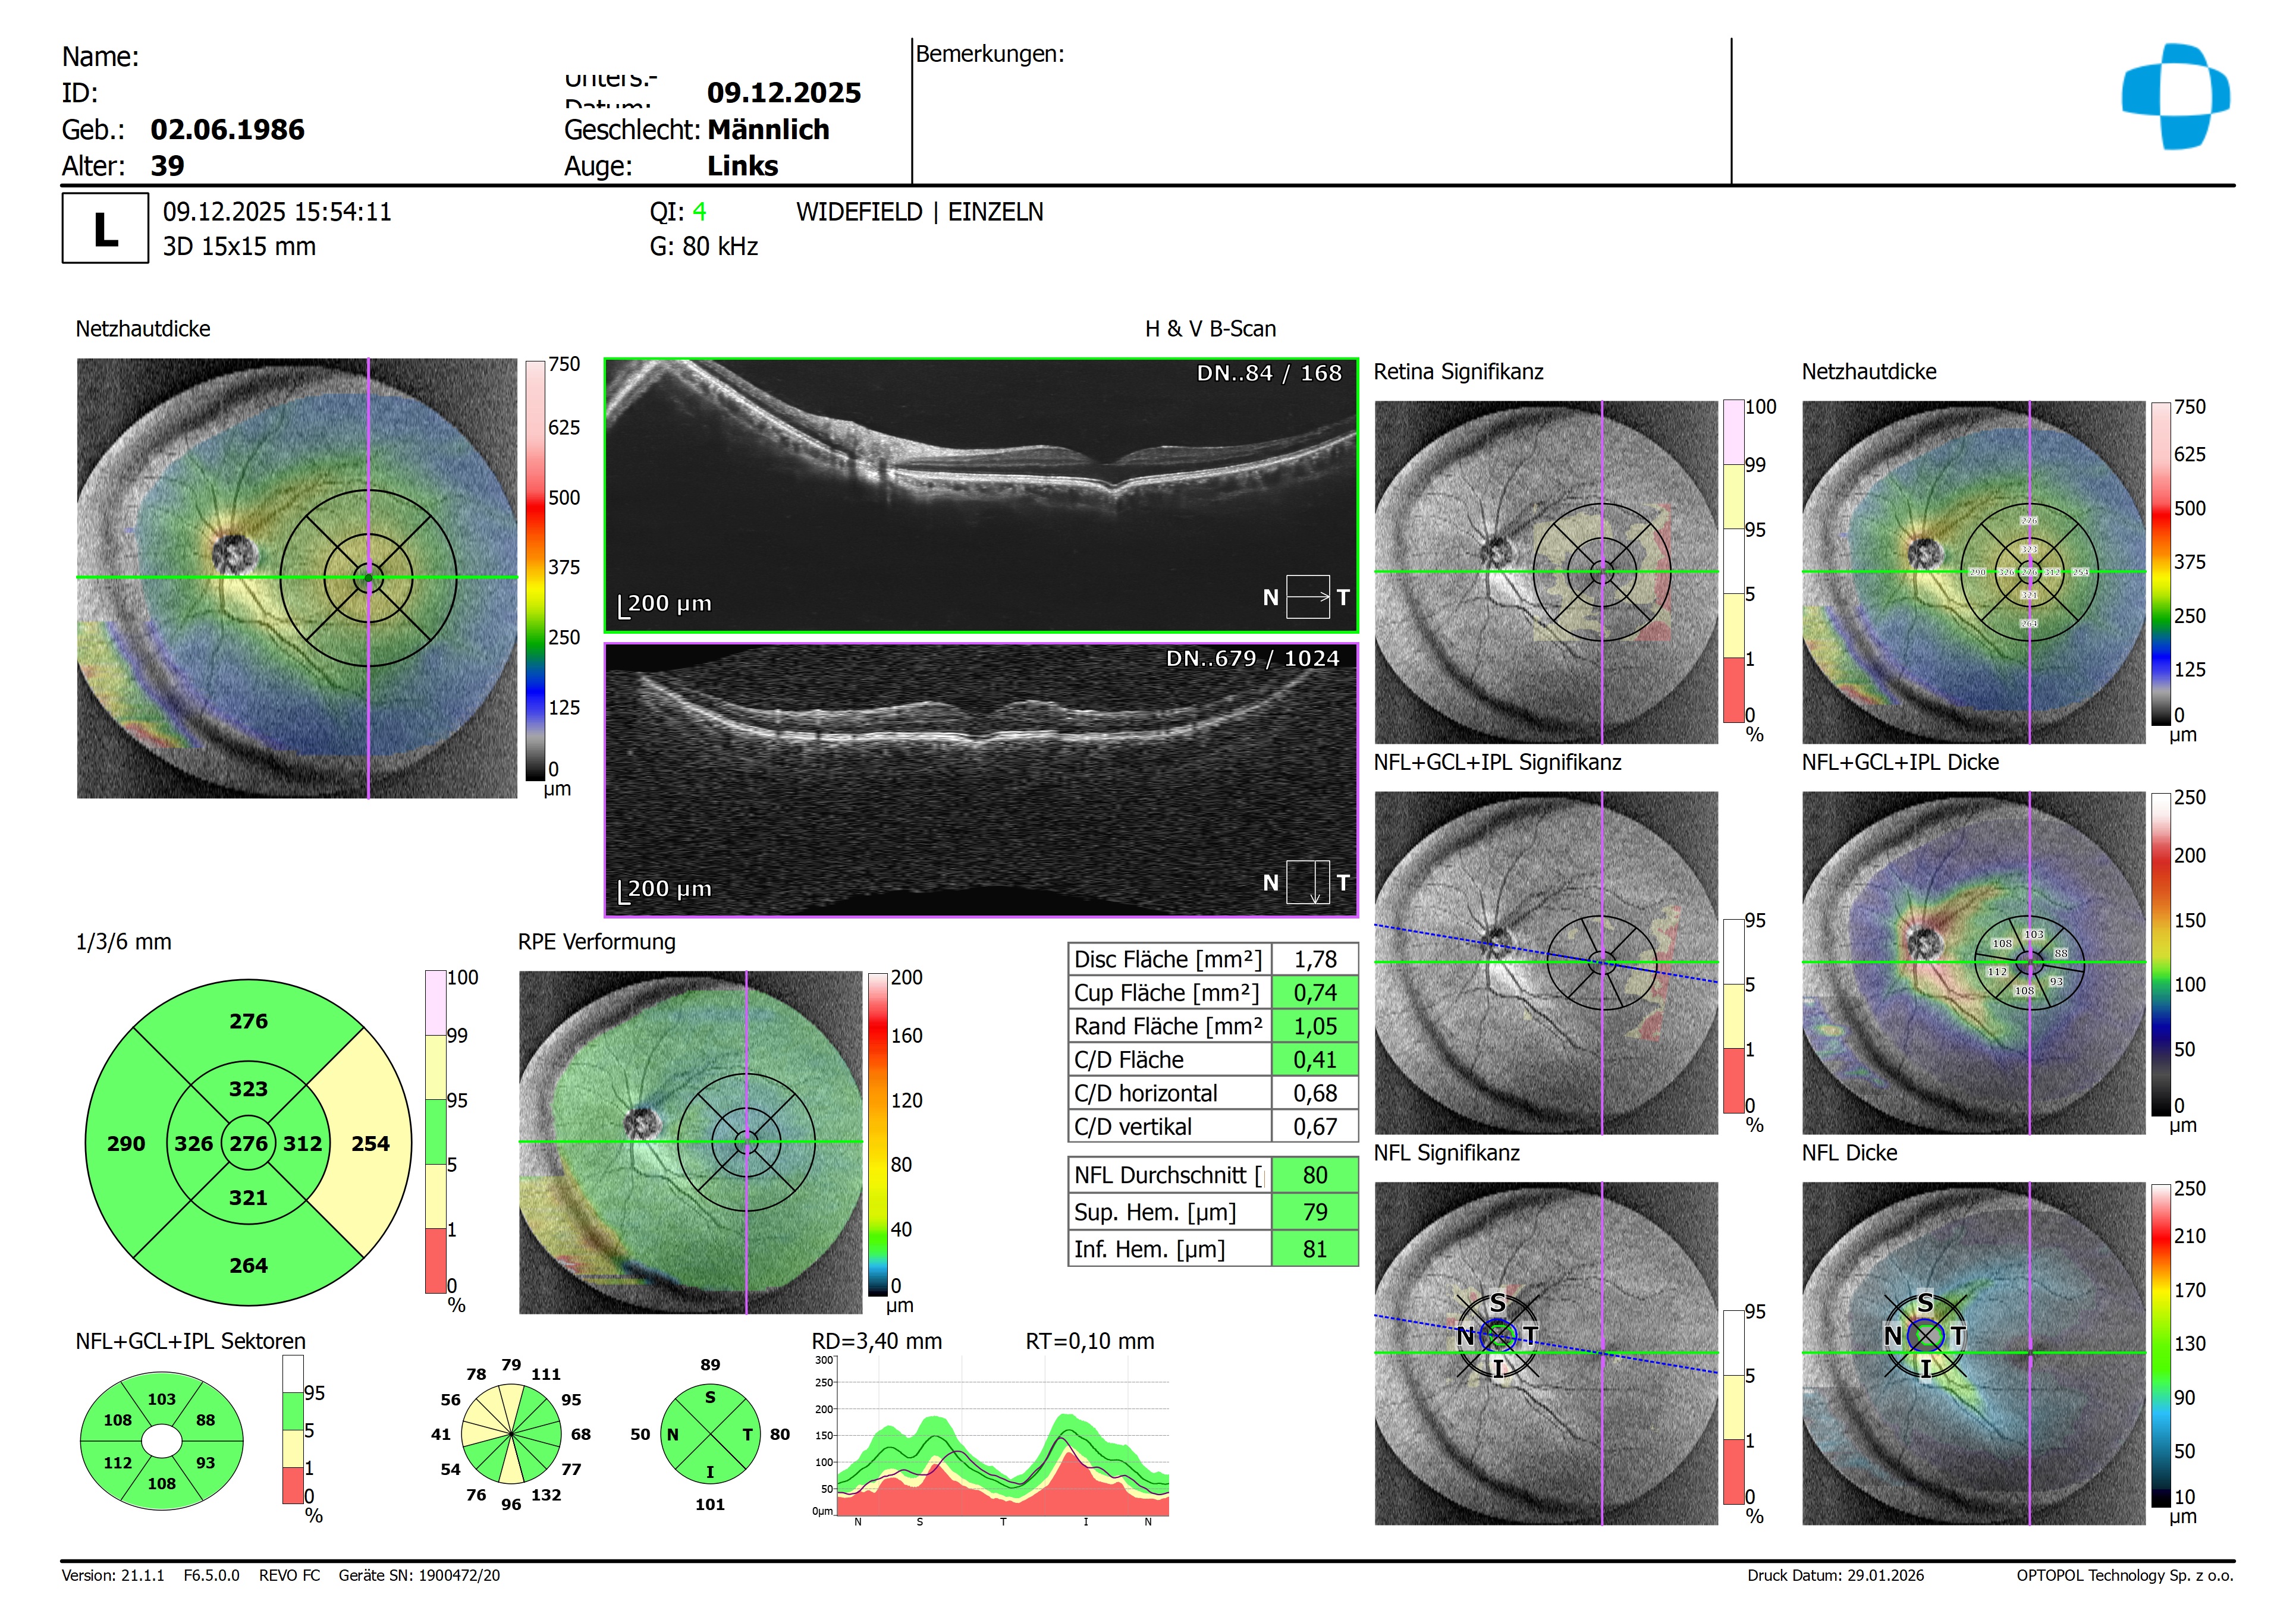

Zur Ergänzung hier noch mal die Widefield Aufnahme links.

Wie bei einer mittleren Myopie üblich haben wir in der Perepherie der NFL eine Dickenreduktion, welche ich jedoch auf Grund der Formänderung des Bulbus als normal einstufen würde.

Auf den vorliegenden Bildern zeigt sich eine atypische Veränderung der Bulbusform im zentralen Foveabereich. Der Bulbus erscheint dort leicht eingezogen, was die beschriebene konkave Konfiguration der äußeren Netzhaut- und Aderhautstrukturen gut erklärt.

Meiner Interpretation nach handelt es sich hierbei weniger um eine pathologische Veränderung als vielmehr um eine anatomische Anomalie, die am ehesten im Sinne eines Mini-Staphyloms zu deuten ist. Beruhigend ist in diesem Zusammenhang, dass sowohl der Netzhautbefund als auch der Visus unauffällig sind.

Differentialdiagnostisch – wie von Enno bereits erwähnt – könnten erworbene Schäden wie eine Maculopathia solaris oder ein Laserschaden in Betracht gezogen werden. In diesen Fällen wäre jedoch typischerweise mit einem deutlichen funktionellen Defizit zu rechnen, das vom Patienten auch als positives Skotom wahrgenommen würde. Zudem zeigt sich bei beiden Entitäten charakteristischerweise ein scharf begrenzter, „wie ausgestanzt“ wirkender Defekt des RPE, was hier eindeutig nicht der Fall ist.

Insgesamt gehe ich daher von einer Normvariante ohne pathologischen Zusammenhang aus. Dennoch empfehle ich zur Sicherheit eine Verlaufskontrolle in etwa 6 Monaten inklusive Visuserhebung und OCT.